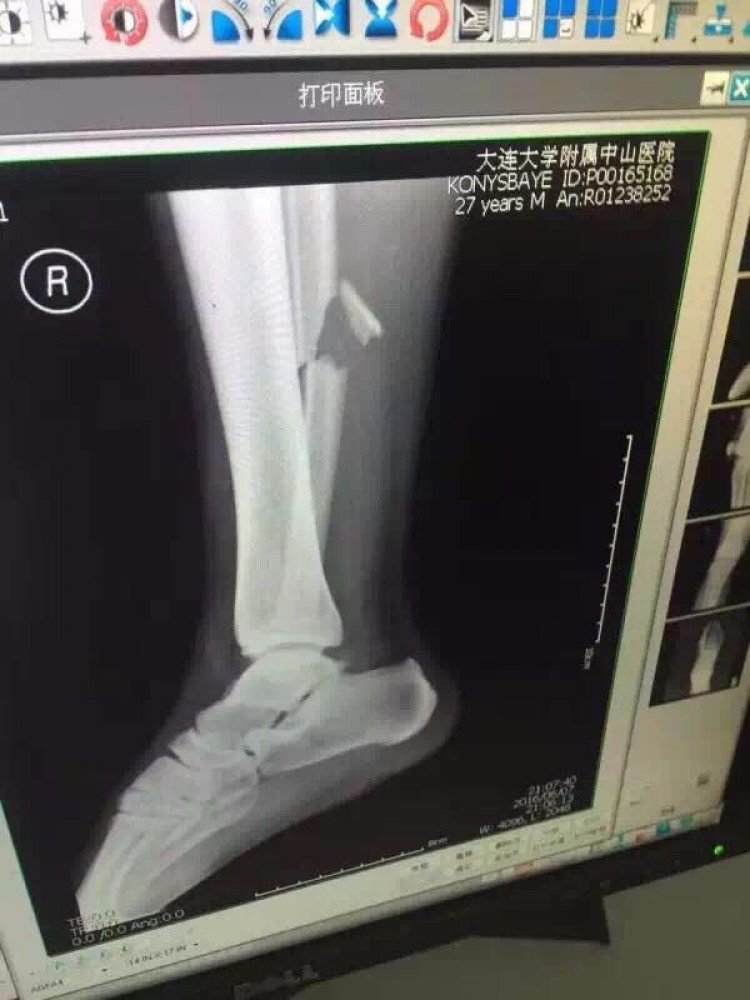

Полузащитник сборной Казахстана по футболу Улан Конысбаев, получивший тяжелейший перелом ноги во вчерашнем товарищеском матче против команды Китая, пробудет в КНР еще семь дней, передает

Vesti.kz. Выяснилось, что в результате перелома у него порваны боковые связки, связки между малой и берцовой костью. Операция длилась 3,5 часа. Отмечается, что Конысбаев сможет ходить только через три месяца. При этом некоторые шурупы в ноге уберут почти через год.